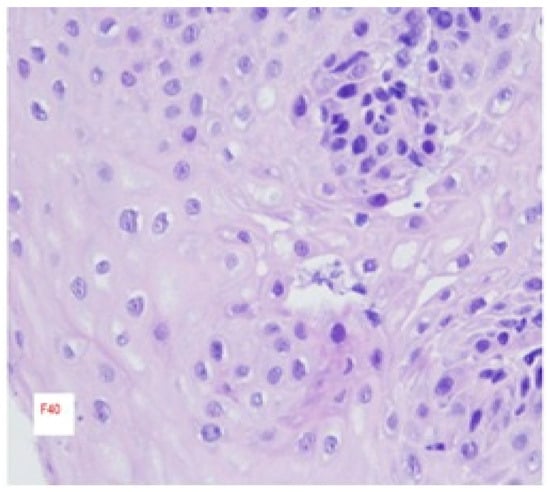

3. Histopathologic Features

- Primary histologic criterion: Peak eosinophil density of ≥15 eosinophils per high-power field (≈60 eos/mm2) within the squamous epithelium of the esophagus.Supportive features: Basal cell hyperplasia (often >20–30% of epithelial thickness; graded semiquantitatively), eosinophil micro-abscesses, eosinophil surface layering, eosinophil degranulation, dilated intercellular spaces (spongiosis), and lamina propria fibrosis when subepithelial tissue is present. 2